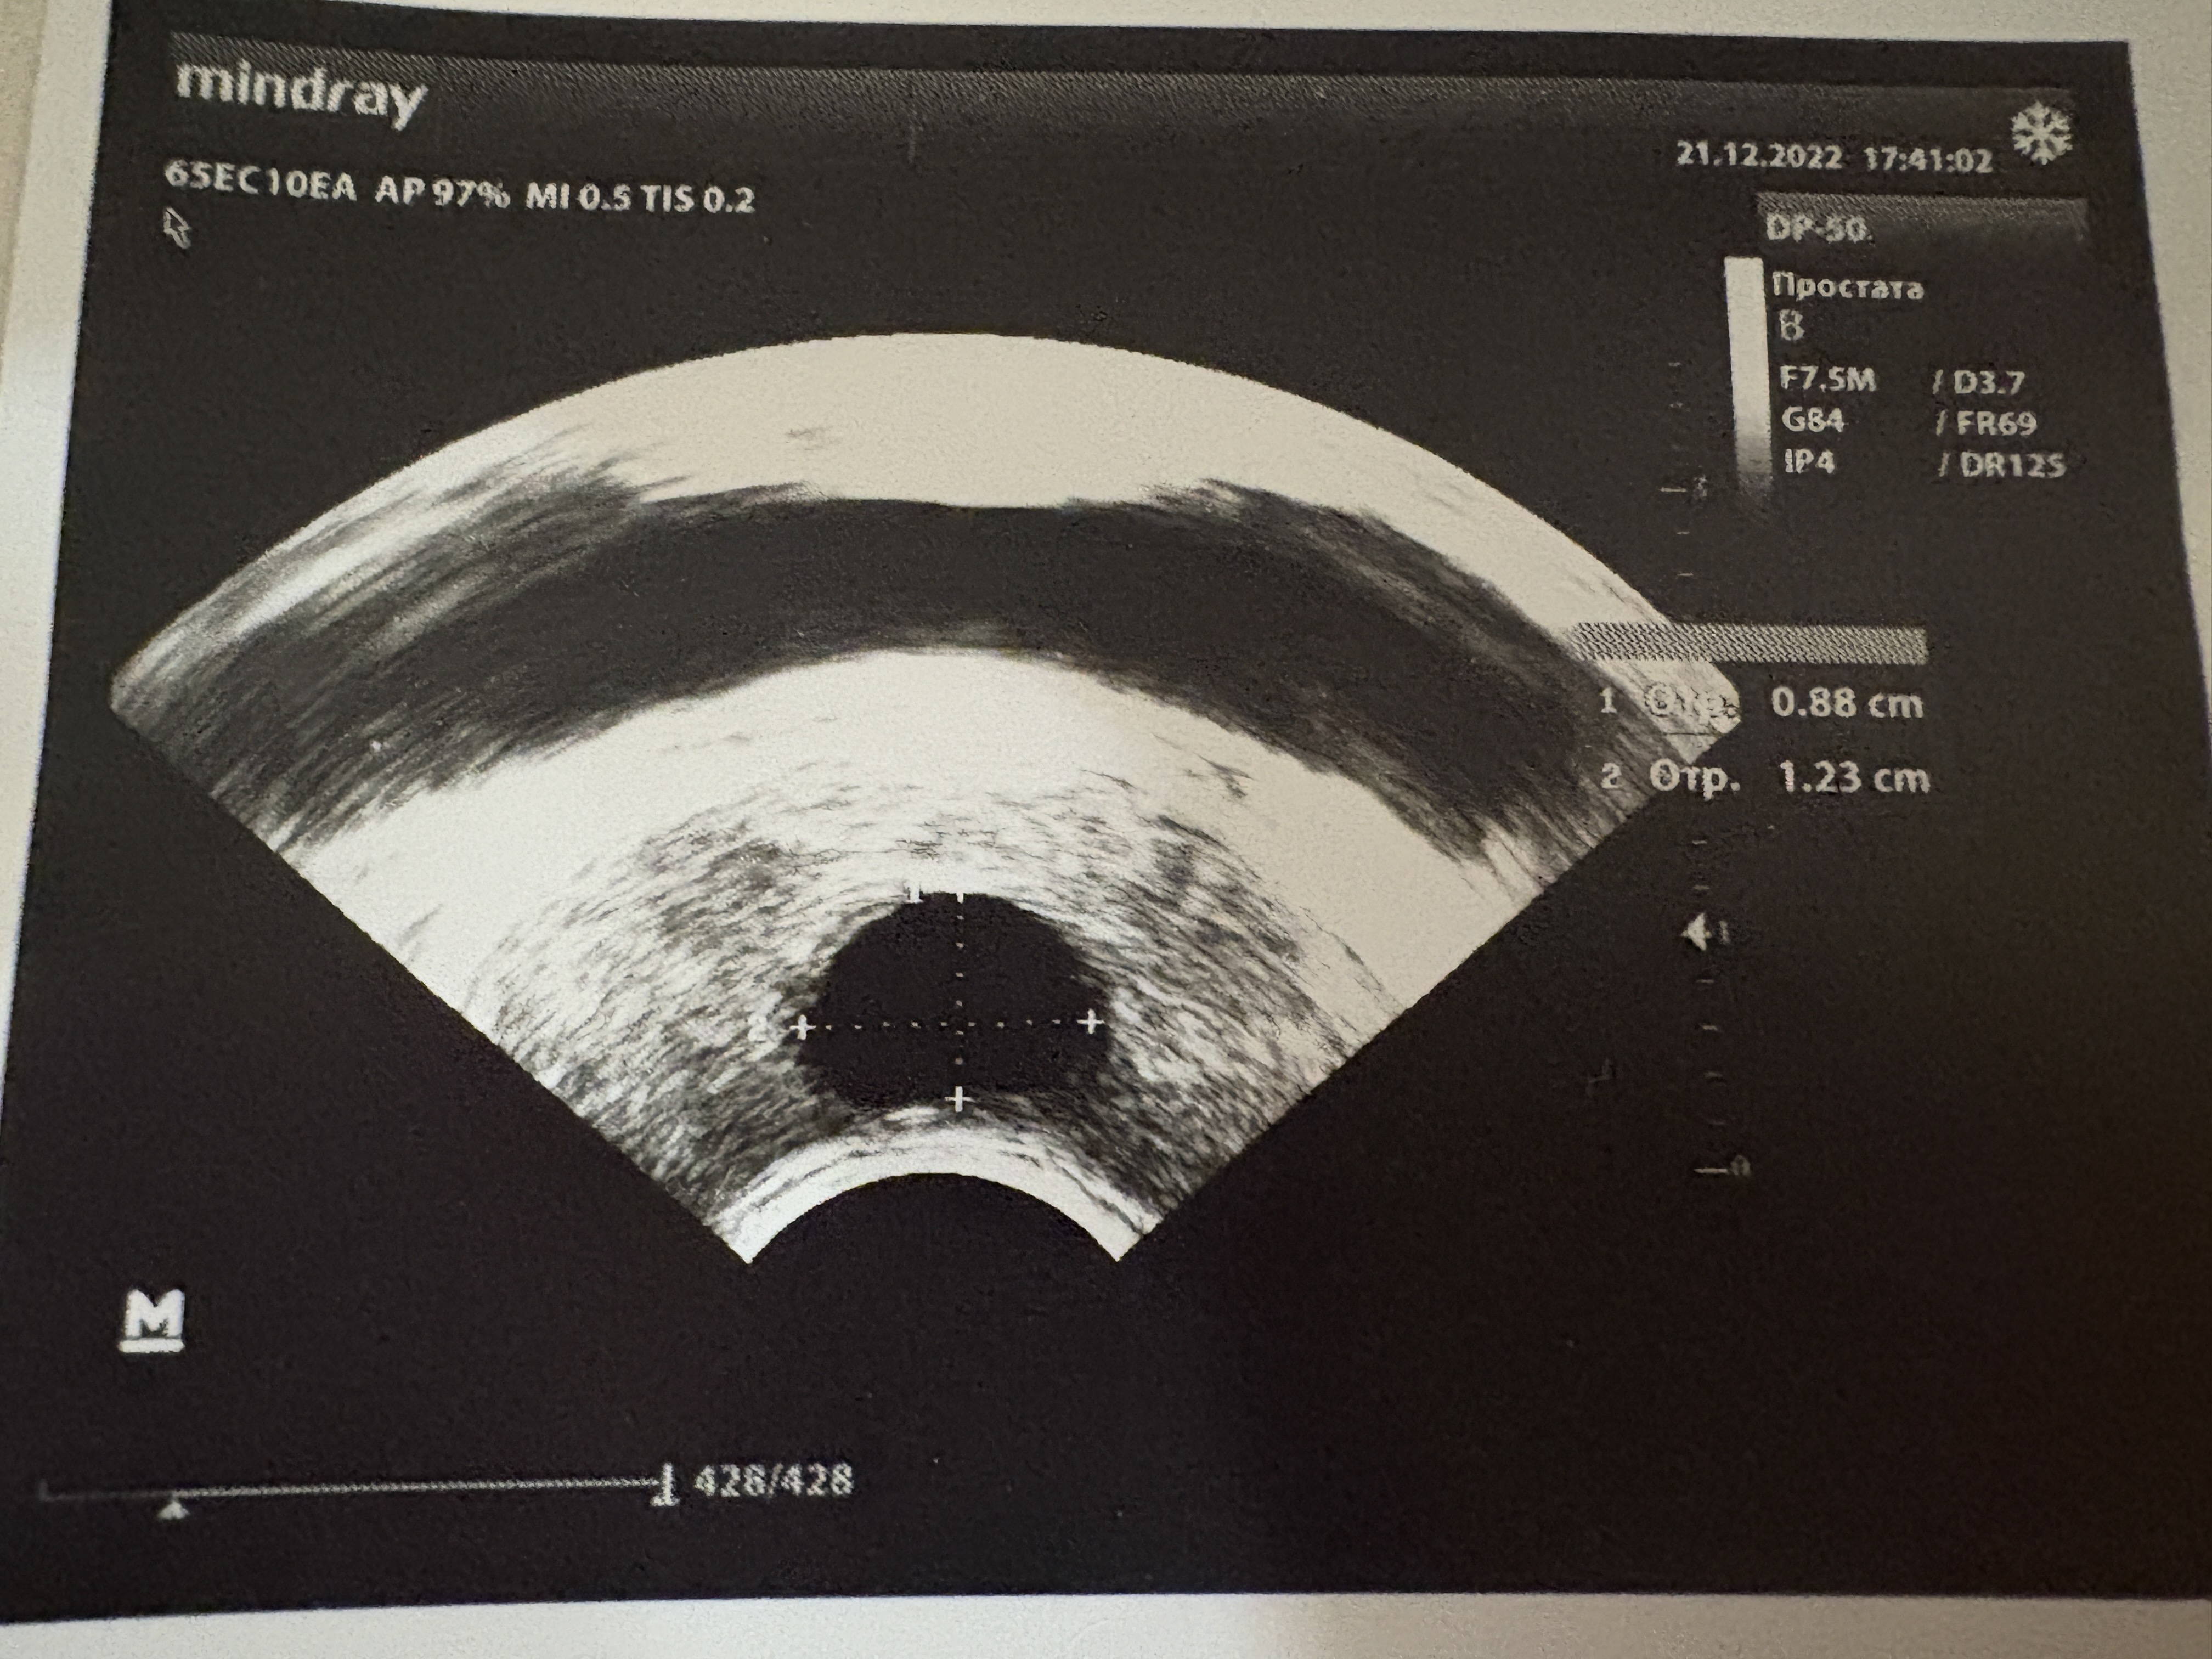

уролог направил сдать анализы и сделать допплерографию. По анализам все в порядке, кроме пролактина: он был в районе 700. На УЗИ-допплера показало, что у меня артериогенная ЭД с вторичной венозной утечкой (как объяснил узист, т.к. нету нормального притока к члену, все утекает, и поэтому член выглядит толще и меньше; фиброза, кстати, нет). В декабре 24-го назначили курс УВТ, и лечиться тадалом 5мг каждый день.